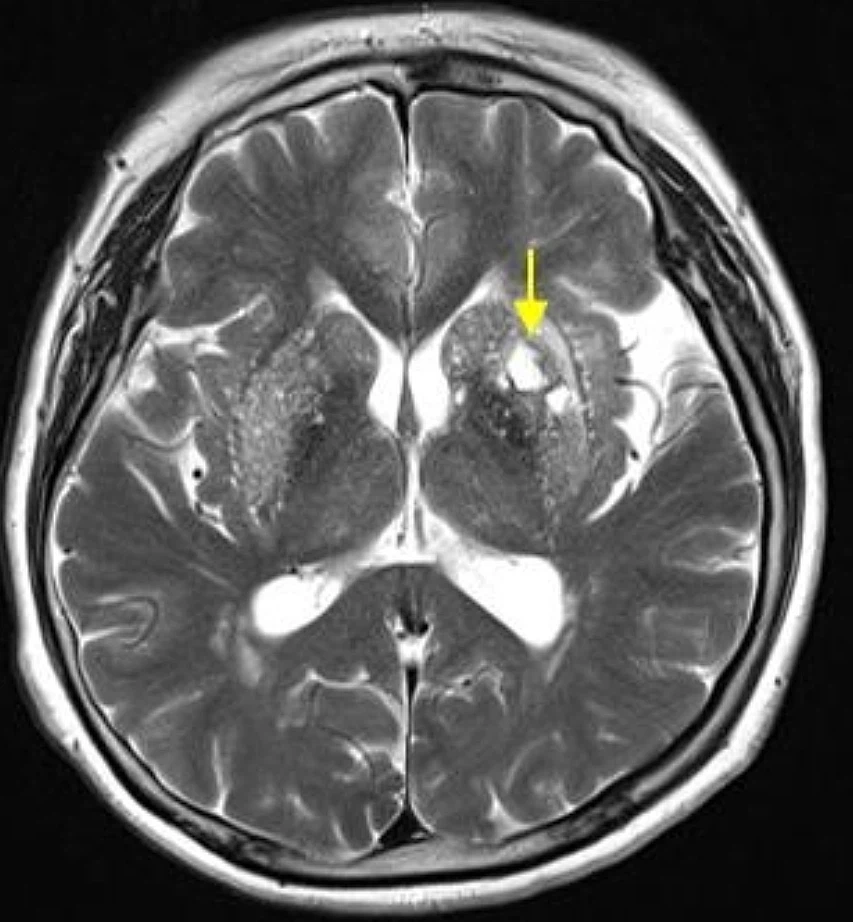

뇌졸중은 뇌에 혈액을 보급하는 혈관이 차단되거나 파손되어 뇌 손상과 인체장애를 일으키는 뇌혈관 질환을 말하고

'중풍' 이나 '뇌혈관 질환'이라고 알려진 게 바로 뇌졸중입니다. 뇌경색이란 용어도 자주 듣게 되는데 뇌경색과 뇌출혈은 뇌졸중의 한 종류로 뇌졸중 중에 뇌경색, 뇌출혈이 포함된다고 볼 수 있습니다.